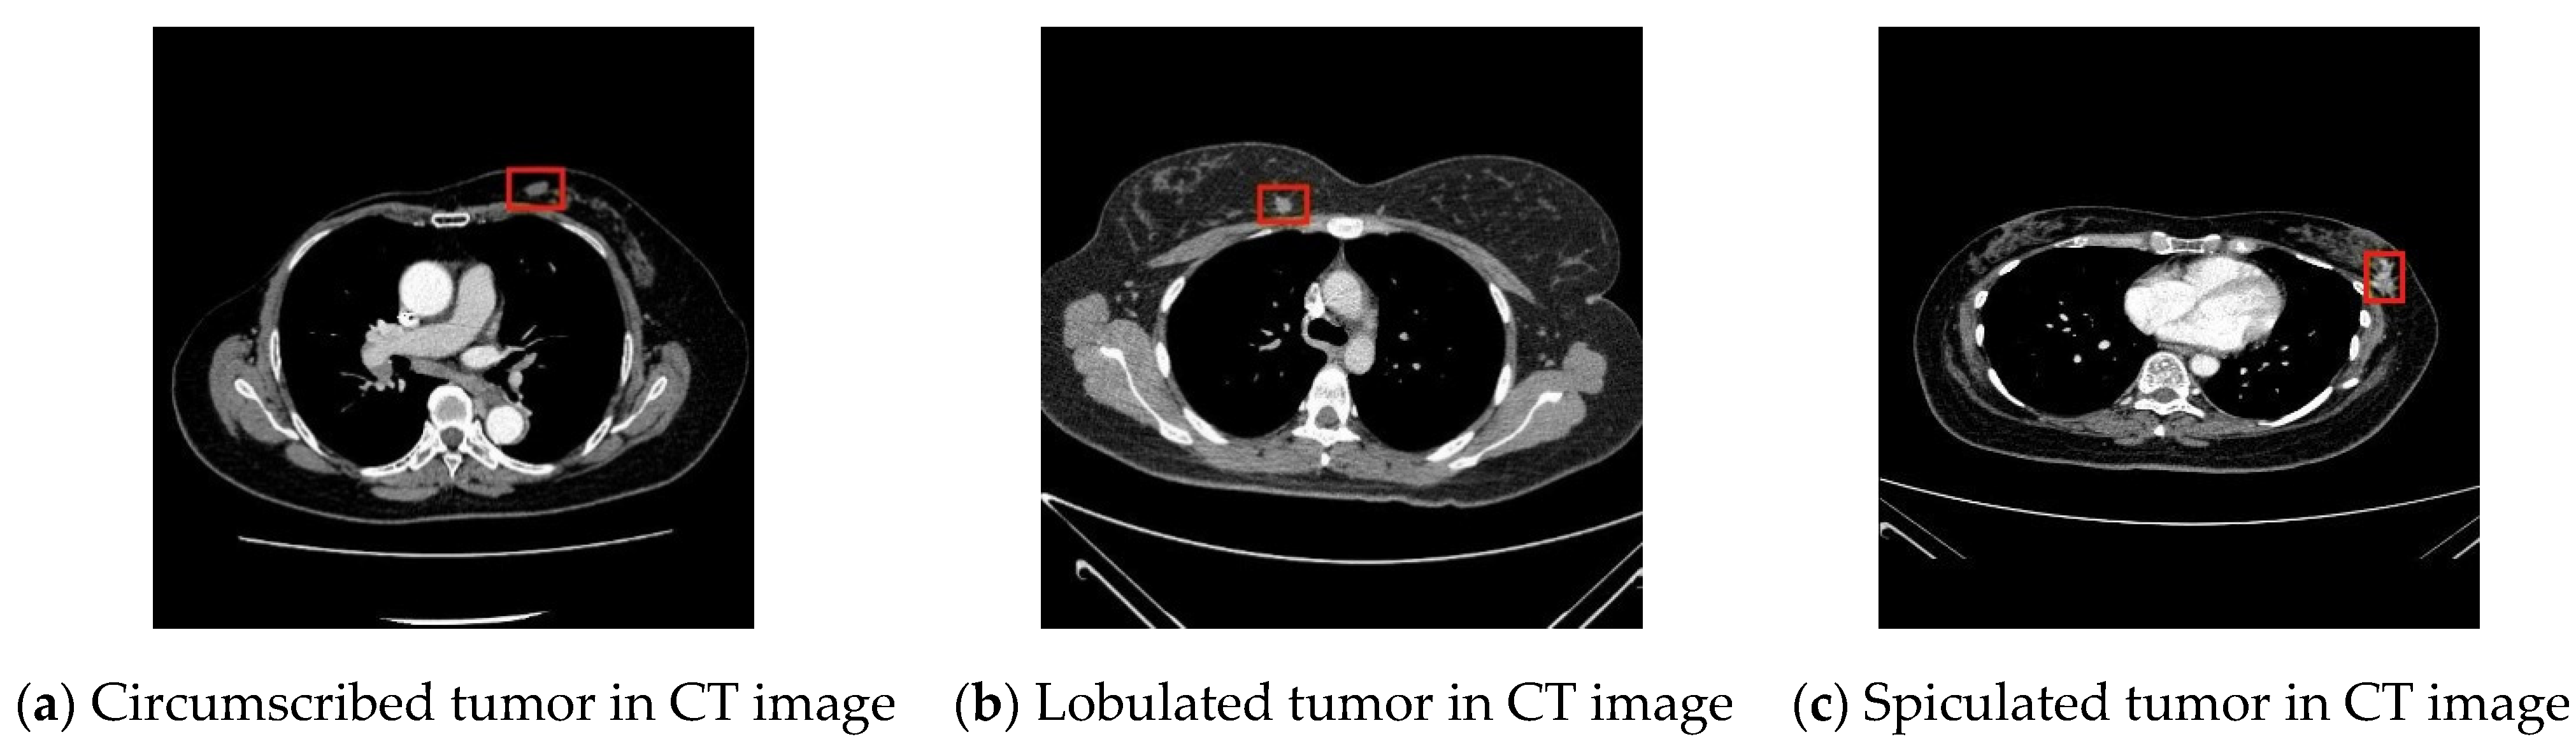

In this study, breast tumor images were divided into three types according to features of their margins [29,30,31], namely, circumscribed tumors, lobulated tumors, and spiculated tumors, as shown in the Figure 1.

Figure 1.

Types of breast cancers.